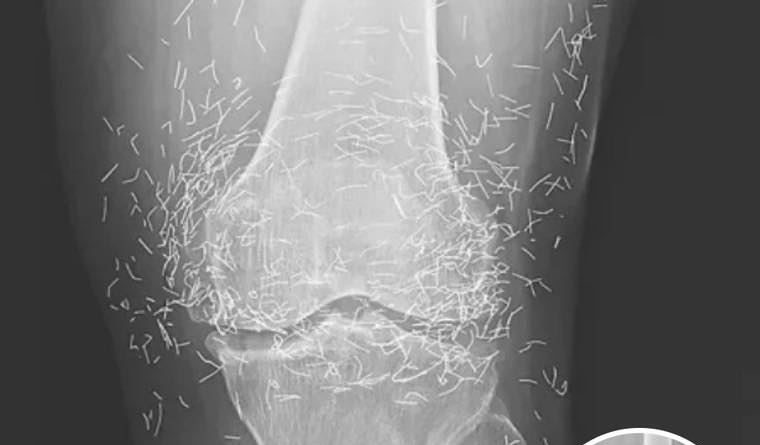

Doctors Stunned After Looking At This X-Ray Of Woman Suffering Joint Pain

A routine hospital visit turned into a surprising discovery when a 65-year-old woman in South Korea underwent an X-ray for